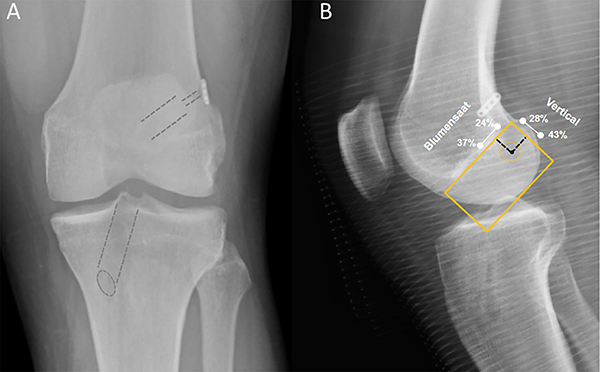

En las radiografías de frente y perfil de la rodilla se evaluaron los siguientes parámetros: 1) posición del túnel femoral; 2) posición del túnel tibial y 3) ubicación del botón cortical femoral. La posición del túnel femoral fue analizada con la grilla de Bernard y Hertel. A través de esta grilla se puede reconocer la línea superior que representa la línea de Blumensaat en toda la anchura del cóndilo, la línea más posterior representa una línea perpendicular a la primera, que es la longitud del cóndilo.

La posición ideal para la salida del túnel femoral es en el 35% de la línea vertical (28 a 43%), 0% es la cortical proximal, y un 29% en la línea de Blumensaat (rango 24 a 37%), siendo 0% la cortical posterior8 (fig. 1A). La posición del túnel tibial en la radiografía de perfil fue evaluada con la grilla de Stӓubli y Rauschning, la posición ideal para la salida del túnel tibial en la línea anteroposterior es en el 42% (rango 39 a 46%), considerando 0% la cortical anterior. En la radiografía de frente se evaluó la salida del túnel tibial en el platillo tibial de medial a lateral, la posición ideal de la salida del túnel es en el 48% (rango 41 a 52%), considerando 0% la cortical medial (fig. 1B). Finalmente, se evaluó la ubicación del botón cortical femoral, en relación a la cortical femoral, midiendo la interposición de partes blandas entre el botón y la cortical en milímetros.

Figura 1: A) Radiografía frente en el postoperatorio inmediato RLCA de rodilla izquierda, se pueden observar los túneles tibial y femoral (líneas punteadas). Botón cortical de fijación femoral en buena posición. B) Radiografía perfil en el postoperatorio inmediato de rodilla izquierda. El centro del túnel femoral se indica con un punto negro. La posición ideal es en el 35% en la línea vertical (28 a 43%) y un 29% en la Blumensaat (rango 24 a 37%).